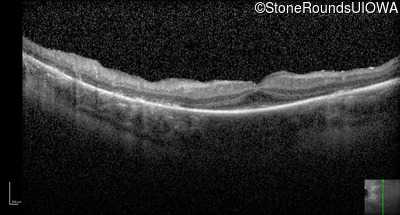

Optical Coherence Tomography - Right - 20/50

Exemplar / OCT Stack

Optical Coherence Tomography - Right - 20/63